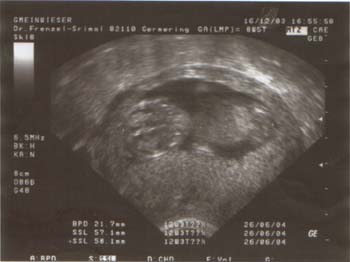

Am Dienstag, den 22.06.04 um 5.30 Uhr in der Früh, hab ich dann

gemerkt, dass ich leichte Wehen habe, im Abstand von etwa 12 Min. Markus rief in der Arbeit an das es warscheinlich los geht und er deshalb nicht in die Arbeit kommt. Dann haben wir ganz langsam die

Sachen zusammen gesucht, Fabian zu Mama & Peter gebracht und anschließend gings ab in die Klink nach Pasing (11.15 Uhr). Dort waren bei dem CTG nur ganz leichte Wehen zu erkennen.

Aber wir sollten in der Klink bleiben. Während wir auf die stärkeren Wehen gewartet haben, sind wir Treppen gestiegen, haben uns im Cafè gestärkt und ich hab mich in der Badewanne entspannt.  Um etwa 17.00 Uhr ging es dann dem Ende zu.

Die Wehen wurden ziemlich stark und darum bekam ich ein Schmerzmittel das angeblich leicht benebelt. *lol* Um 19.14 Uhr (nach vielen Wehen) war “....der kleine Raphael” auf der

Welt (und ich war high von dem Schmerzmittel). Ich hab die Nabelschnur durchschnitten & Markus hat ganz genau die Nachgeburt betrachtet !!! *lecker* Mehr Fotos von Raphael könnt ihr Euch auf seiner Fotoseite anschauen.